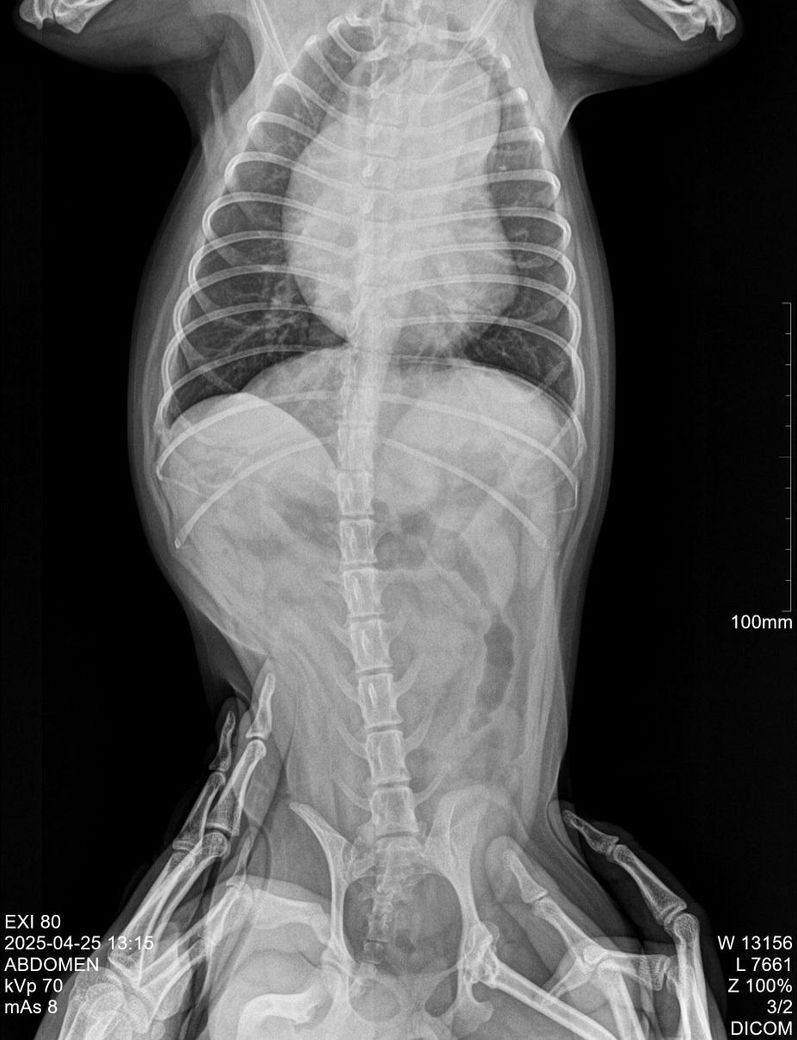

강아지 최근에 찍은 엑스레이 한번 봐주세요

올해 4월 에 엑스레이 찍어보니 심장이 커진거같다고 pda의심된다고는 하는데 아닐수는 있다고는 하세요.

혹시 엑스레이 상으로 알수 있는 점이 있나요?

이 사진 한장으로는 어떤것도 진단할 수 없습니다. 방사선 검사는 기본적으로 90도 각도로 2장의 사진이 최소한으로 필요하고, 흉부는 흉부 방사선 검사로 판독하는것이지 복부 방사선 사진으로 판단하면 안됩니다. 심장 질환은 심장 초음파 검사가 확진 수단 즉, golden standard 검사이니 심장 초음파 검사를 받고 그 결과에 따라 후속 조치 진행하시기 바랍니다.